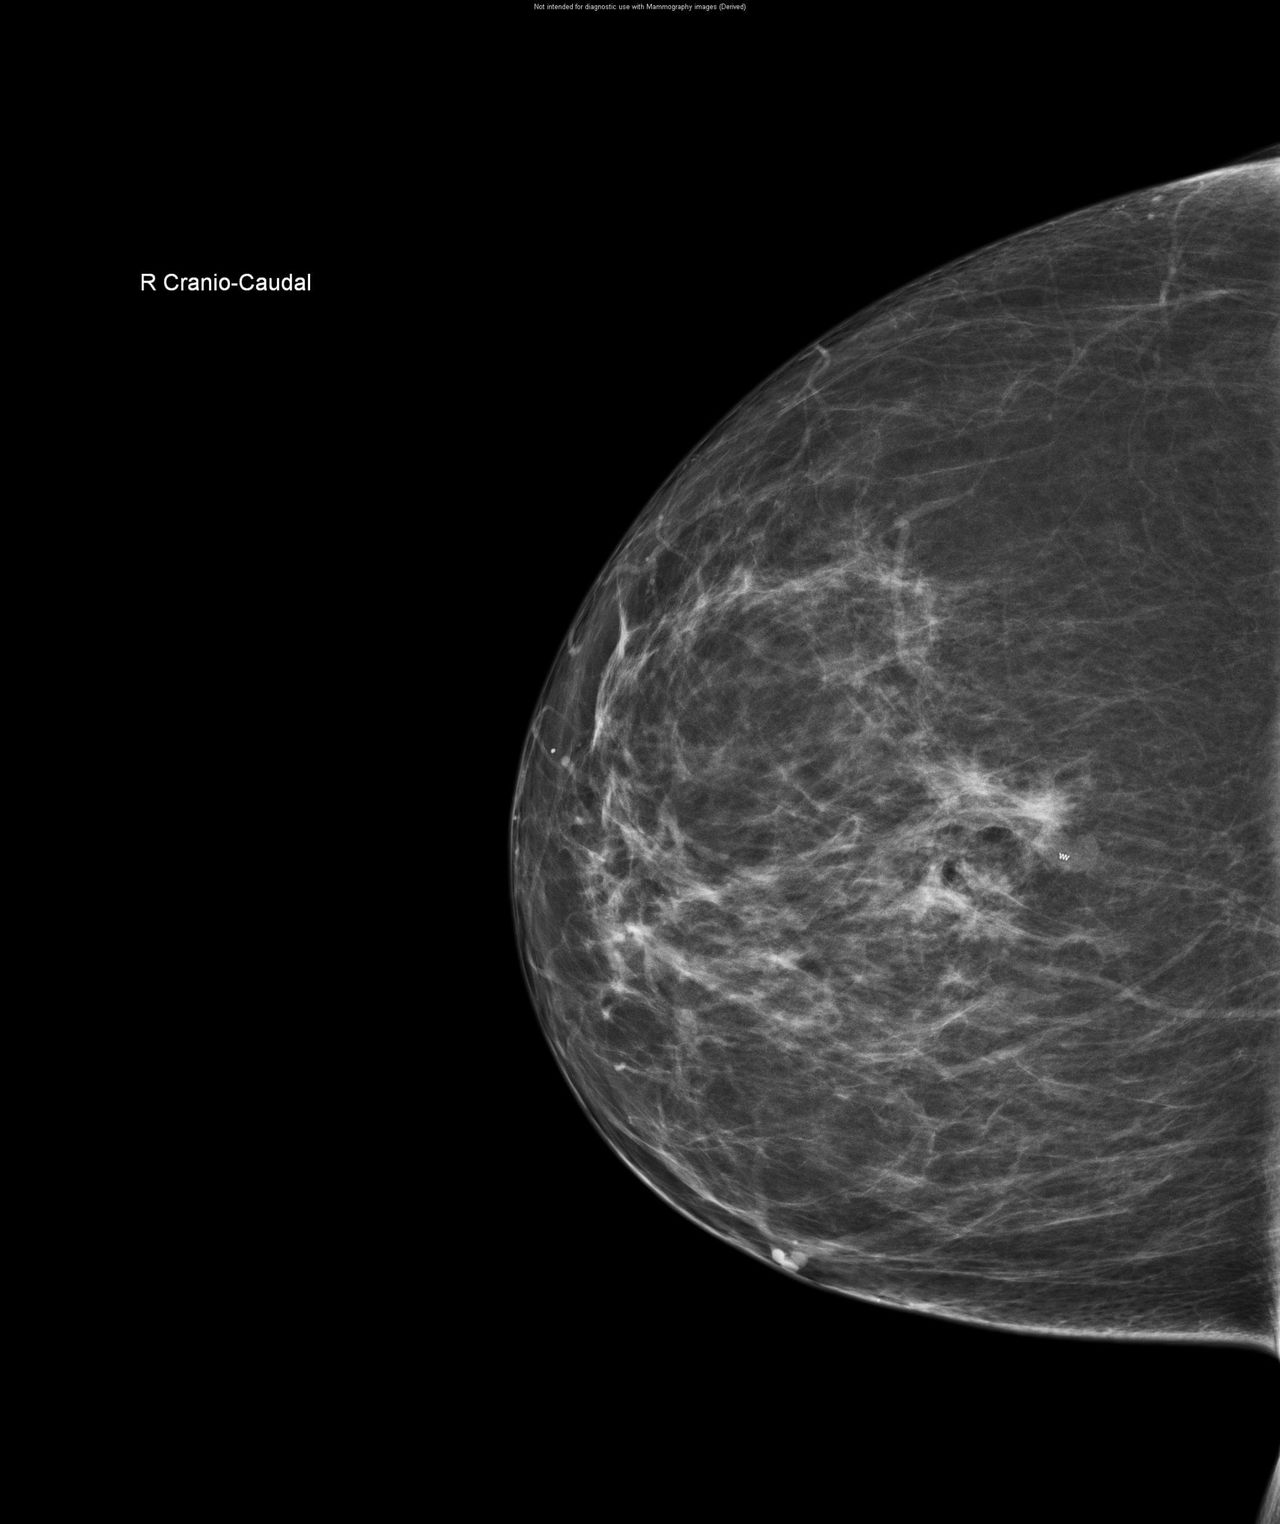

CESM is an advanced form of mammography that uses a safe dye injected into the bloodstream. This dye highlights areas of concern within the breast, giving clinicians a much clearer and more detailed image than a traditional mammogram.

“Sometimes it can be difficult to interpret a mammogram, especially in patients with dense breast tissue”, Nicole explains. “It’s a bit like looking for a cloud in a sky full of clouds. The contrast helps remove that ‘noise’ and shows us exactly what’s going on inside the breast.”

One of the biggest advantages of CESM is that it can be carried out during the patient’s breast clinic appointment and reviewed by a radiologist straight away. Before CESM was introduced, patients with unclear mammogram results often faced a longer wait for further tests, such as an MRI scan, to gather more information.